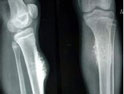

骨巨細胞瘤

骨巨細胞瘤在1940年首次被Jaffe發(fā)現(xiàn),為常見的原發(fā)性骨腫瘤之一,來源尚不清楚,可能起始于骨髓內(nèi)間葉組織。骨巨細胞瘤具有較強侵襲性,對骨質(zhì)的溶蝕破壞作用大,極少數(shù)有反應(yīng)性新骨生成及自愈傾向,可穿過骨皮質(zhì)形成軟組織包塊,刮除術(shù)后復(fù)發(fā)率高,少數(shù)可出現(xiàn)局部惡性變或肺轉(zhuǎn)移(即所謂良性轉(zhuǎn)移)。骨巨細胞瘤為低度惡性或潛在惡性的腫瘤。本病多在20~50歲發(fā)病,女性高于男性。骨巨細胞瘤的原發(fā)部位多發(fā)生在骨骺,隨病灶的擴大逐漸侵及干骺端。骨巨細胞瘤多侵犯長骨,以股骨下端及脛骨上端為最多。